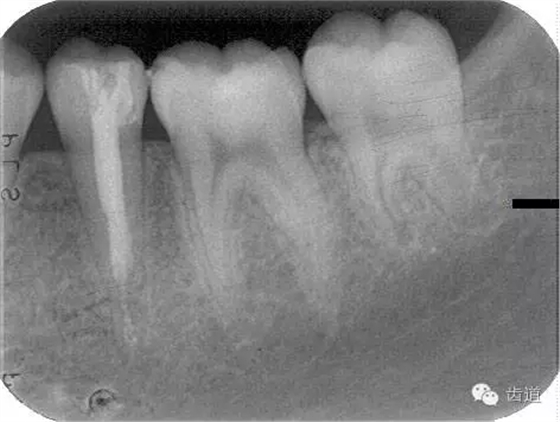

1.術(shù)前X線片

術(shù)后

術(shù)前